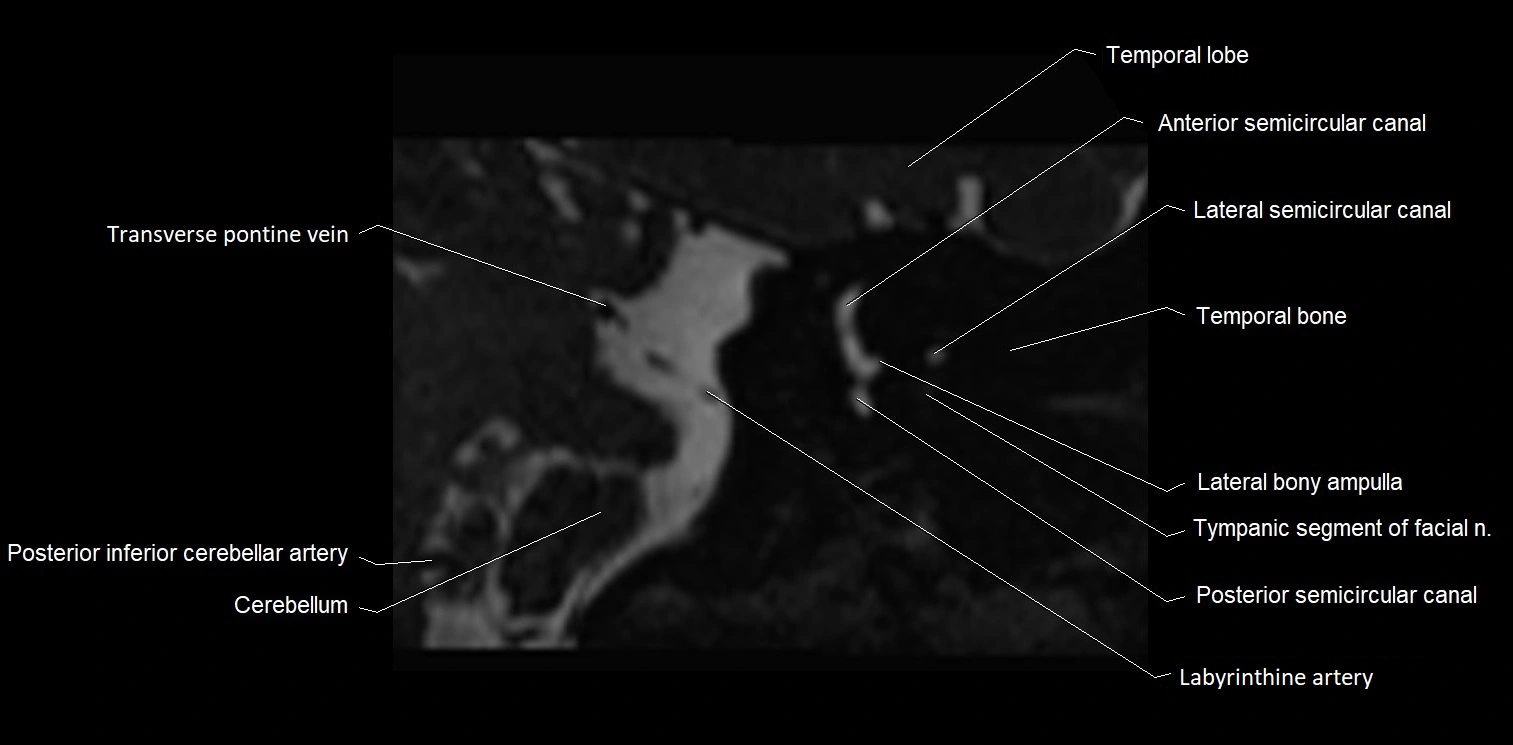

MRI images

image